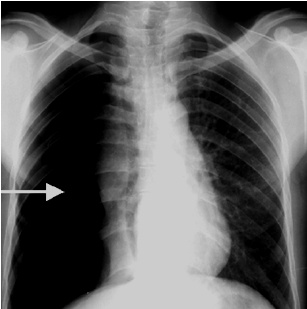

解題:箭頭所指部分漆黑一片,根據(jù)公式得出氣胸